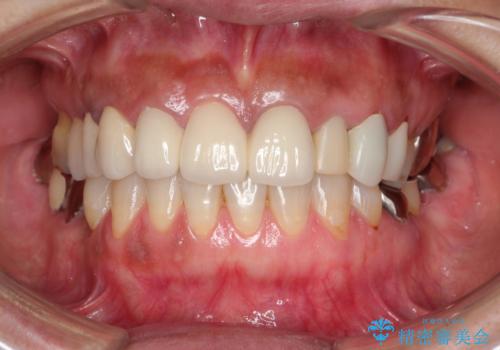

長い間億劫で手を付けていなかったものの、仮歯にした時点から自然な口元となり、視線が気にならなくなったとのことでした。

出来上がってきたセラミッククラウンはまるで自身の歯のようで、患者様には大変満足していただきました。